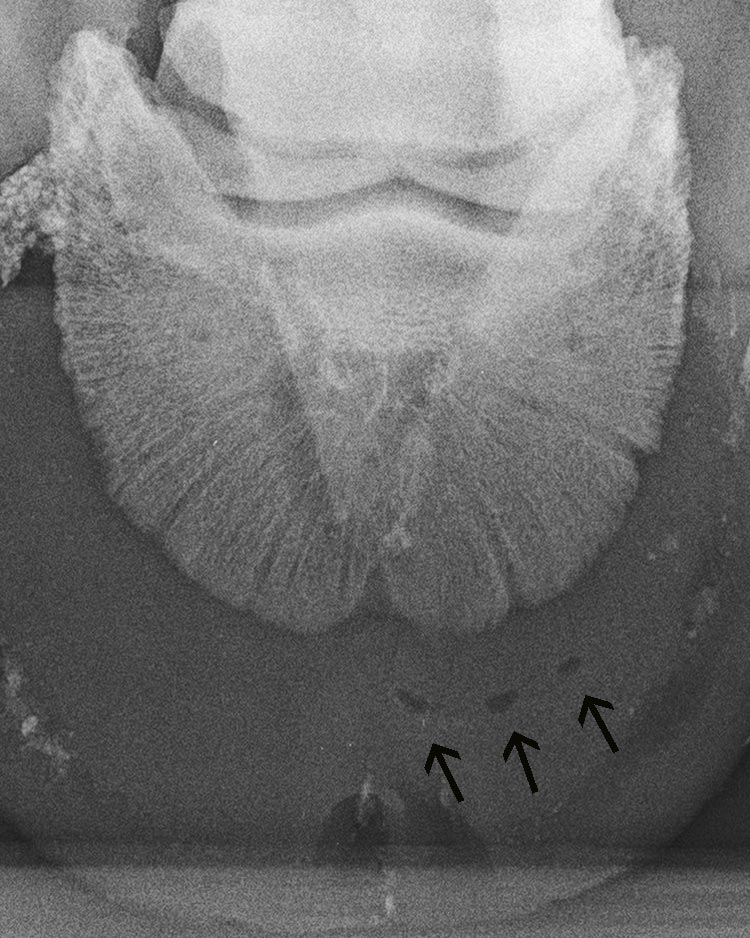

Zehe vorne links - 0°-Aufnahme

sehr tief liegendes Hufgeschwür (Pfeile),

das Hufgeschwür fand erst nach 3 Angußverbänden Abfluß